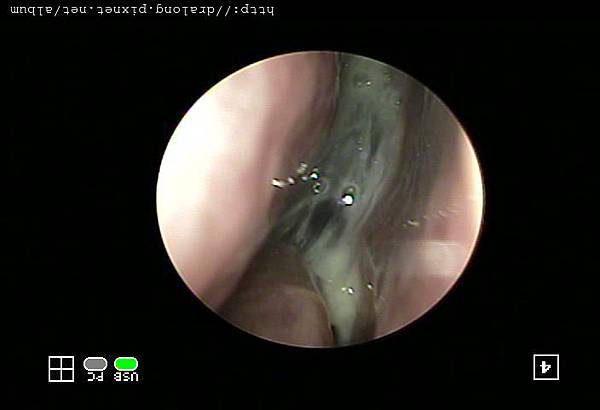

急性鼻竇炎常見原因是因為急性上呼吸道感染(感冒)而引起的次發性細菌感染所造成,少數則是因上排牙齒蛀牙感染引起。當有鼻子過敏,鼻中隔彎曲,鼻內異物,腫瘤,鼻息肉,或過度使用解鼻塞噴劑(像歐X鼻),就更容易會造成鼻竇炎。所以只要有感冒就別忘了會有鼻竇炎的風險。鼻竇炎的主要症狀有鼻塞、流膿鼻涕、頭痛、眼睛或臉頰漲痛、嗅覺變差、鼻水倒流、咳嗽(可咳出膿痰)等症狀,更常使人頭昏昏沈沈,注意力難以集中、情緒低落、記憶力減退,影響工作,睡眠和生活。而小孩子更容易因為鼻竇炎而讓中耳炎,咳嗽拖了好幾個禮拜都沒明顯改善。更嚴重者會產生鼻竇周圍骨髓炎,頑治性中耳炎,眼窩蜂窩組織炎、海綿竇栓塞及嚴重腦膜炎和腦膿瘍等併發症。

鼻竇炎的致病菌是一般常見的上呼道內的細菌包括肺炎雙球菌、嗜血性流行性感冒桿菌、卡他莫拉菌等。所以在治療上主要是選擇對上述細菌有效的抗生素,使用正確的劑量及完整的治療時間,才能成功達到治癒疾病。急性鼻竇炎的用藥時間需要1~2週,慢性鼻竇炎則會更久(4~6週)。要是慢性鼻竇炎藥物治療效果不好更嚴重者會產生,有時候須搭配生理食鹽水清洗鼻子,甚至需要更進一步接受手術的治療。所以要是感冒歷久不癒時,最好立即診治,以免由急性鼻炎發展為急性鼻竇炎,甚至變成慢性鼻竇炎可就麻煩了。